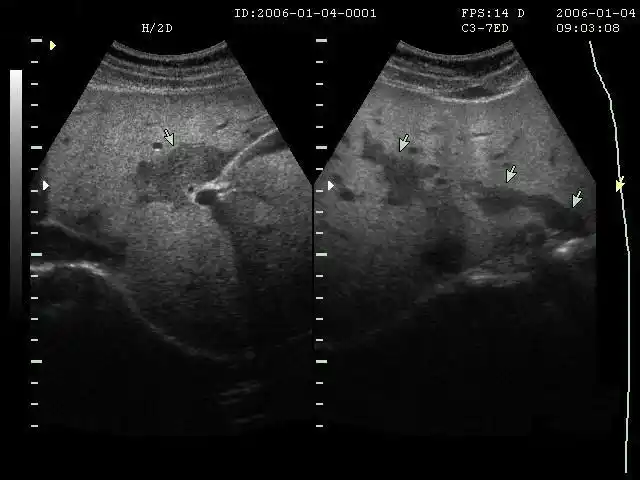

【超乎想像】从超生的角度带您了解脂肪肝

脂肪肝b超影像图

脂肪肝—"后段声衰减"图10 脂肪肝—"衰减"另外一个超声可以诊断的